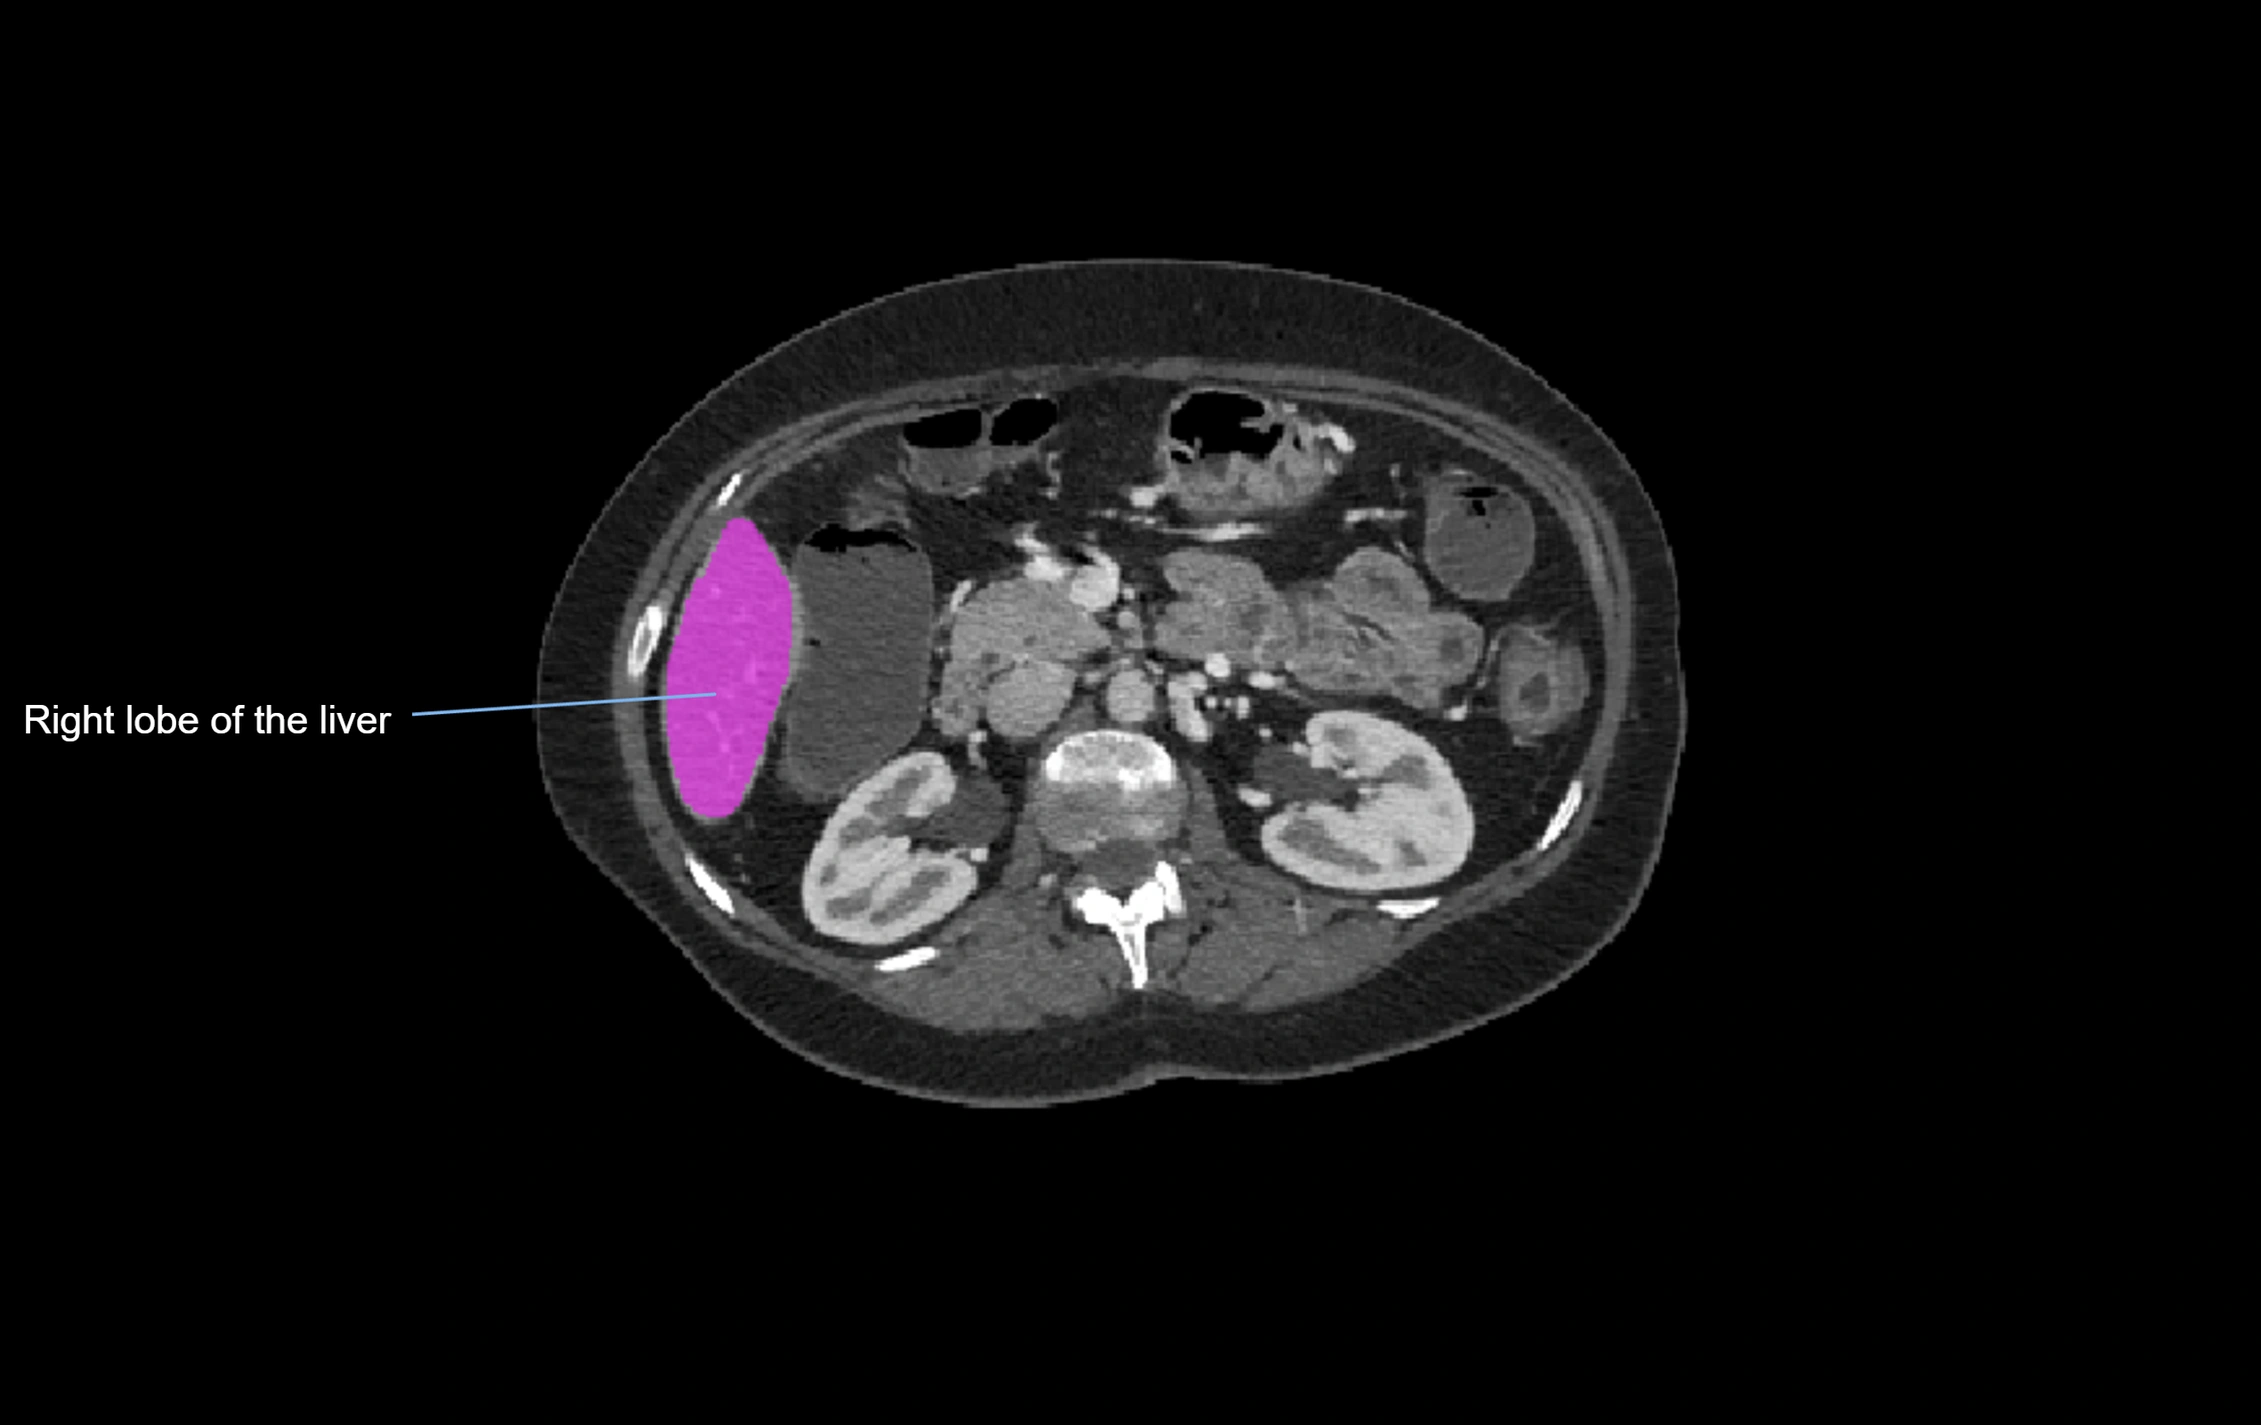

CT Image

image